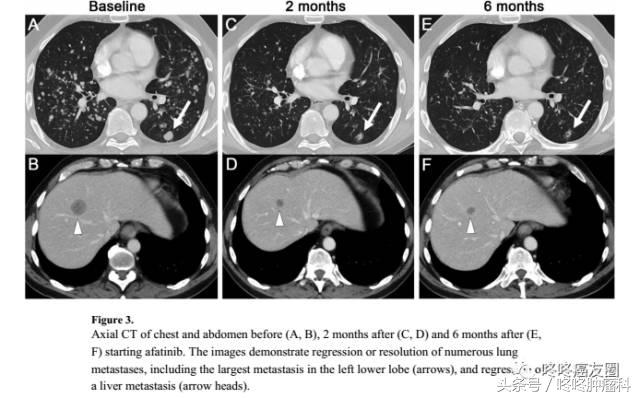

这是一个携带有HER2基因20外显子775位YVMA插入突变的病人,在接受了四五种其他药物的治疗纷纷失败以后,尝试了阿法替尼,用药2个月后,病灶就明显缩小了。

这是一个携带有HER2基因20号外显子780位GSP插入突变的病人,在接受了2种不同的化疗方案累计20个月后,疾病进展,尝试了阿法替尼,肺部病灶就明显缩小;不过不久后,就出现了脑部的新发病灶,医生选择了手术切除。目前病人依然健在。